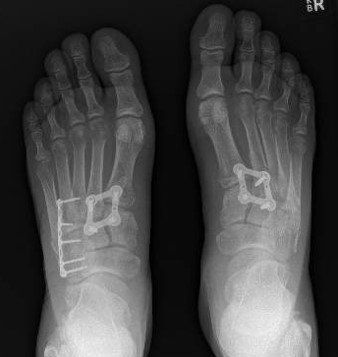

- If there is any "instability", surgery is usually recommended to restore alignment and stability. This is proven to reduce the chance of long-term midfoot pain and osteo-arthritis.

Diagnosis of Lisfranc Midfoot Injury

- imaging investigations.